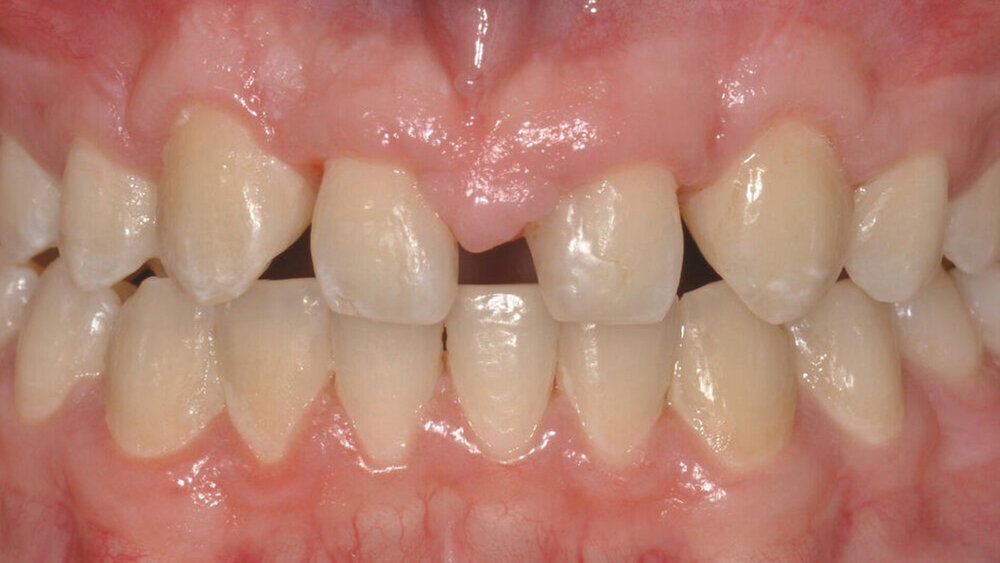

Bei der Erstvorstellung zeigt der Patient ein ausgeprägtes Diastema mediale sowie Restlücken und Asymmetrien im Oberkieferfrontzahnbereich nach kieferorthopädischer Therapie alio loco (Abbildung 1). Aufgrund mangelnder Adhärenz konnten nicht alle kieferorthopädischen Behandlungsziele erreicht werden, was insbesondere aus ästhetischer Sicht Herausforderungen für den restaurativen Lückenschluss mit sich bringt. Erschwerende Faktoren sind die Verschiebung der Mittellinie, die Achsenneigung der Zähne 13, 12, 22 und 23 sowie die inhomogene Lückenverteilung mit ungleich verteilten Lückengrößen (Abbildung 2). Eine erneute kieferorthopädische Korrektur lehnt der Patient allerdings ab. Subjektiv empfindet er insbesondere das kindliche Erscheinungsbild der lückig stehenden, kurz und klein wirkenden seitlichen Schneidezähne als störend. Ziele der Behandlung sind eine präventionsorientierte, ästhetisch-funktionale Rehabilitation des Oberkieferfrontzahnbereichs und eine Harmonisierung des dentofazialen Erscheinungsbildes.